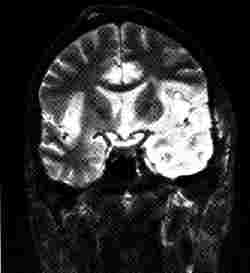

Mediales Keilbeinmeningiom

Aus: Lissner, J., Seiderer, M. (1990)